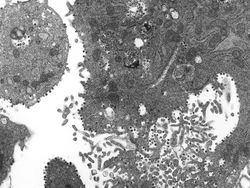

Mikrograf elektron bagian tipis dari virus corona yang tumbuh di dalam sel. Foto: John Nicholls, Leo Poon dan Malik Peiris, University of Hong Kong (Twitter/@hkumed).

Gambar dari Centers for Disease Control and Prevention (CDC) menunjukkan bagian tipis isolat virus corona kemungkinan penyebab penyakit misterius yang dikenal sebagai sindrom pernafasan akut parah (SARS) 2 April 2003 di Atlanta, Georgia. Menurut CDC, virus yang menyebabkan SARS mungkin merupakan virus yang sebelumnya tidak dikenal dari keluarga Coronavirus. Penyakit ini diyakini berasal dari China dan telah menyebar ke seluruh dunia. Foto: CDC/Getty Images

Kisaran diameter virus ini antara 20 nanometer--nanometer adalah seperseribu mikrometer--hingga 1 mikrometer. Foto: CDC/Getty Images

"Setiap sel yang terinfeksi menghasilkan ribuan partikel virus infeksius baru yang dapat terus menginfeksi sel-sel baru," demikian pernyataan University of Hong Kong. Foto: CDC/Getty Images